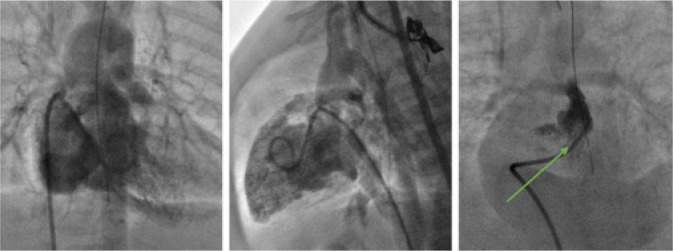

Methods: This prospective, randomized, two-center study included infants with tetralogy of Fallot who underwent surgery between June 2018 and 2022. The patients were divided into two groups - those who underwent stenting of the right ventricular outflow tract (stent group, n=21) and those who underwent modified Blalock-Taussig shunt placement (shunt group, n=21).

Results: In the stent group, a significantly greater increase in Nakata index was observed, with mean values rising from 104.2 to 208.6 mm2/m2, compared to an increase from 107.3 to 169.4 mm2/m2 in the shunt group (P<0.01). According to the mixed model analysis, the rate of growth of the right pulmonary artery in the stent group was 2.05*10-2 z score/day, which was 3.01 times greater than that in the shunt group (P<0.01). The rate of growth of the left pulmonary artery in the stent group was 2.3*10-2 z score/day, which was 1.47 times greater than that in the shunt group (P<0.01). In one patient (4.8%), after 76 days following the stenting of the RVOT, a severe infectious process with sepsis occurred, leading to a fatal outcome. Complete correction in the stent group involved transannular patch repair of the right ventricular outflow tract to the pulmonary artery in 12 patients (60%), while the same procedure was performed in 15 patients (71.4%) in the shunt group (P=0.52).

Conclusion: Stenting of the right ventricular outflow tract provides hemodynamic stabilization and symmetric growth of the pulmonary vascular bed compared to the formation of a modified Blalock-Taussig shunt.